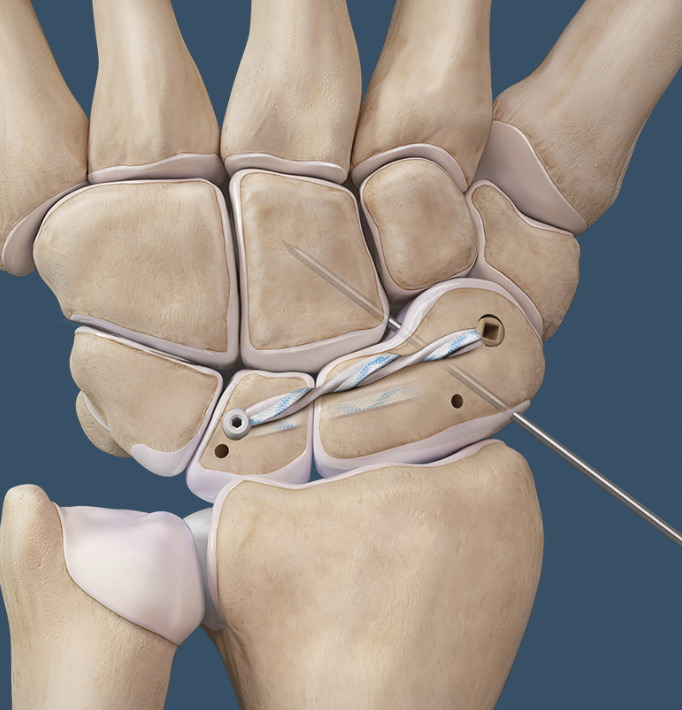

Scapholunate ligament reconstruction / ligamentoplasty

Options

- autograft / allograft ligaments

- internal brace

- bone-retinaculum bone autografts

Open dorsal scapholunate ligament reconstruction

Arthrex all dorsal SL ligament reconstruction with internal brace PDF

Arthrex all dorsal SL ligament reconstruction with internal brace video

Vumedi dorsal SL ligament reconstruction with internal brace video

Arthroscopy techniques dorsal SL ligament reconstruction with internal brace

Interosseous scapholunate ligament reconstruction

Arthrex interosseous SL ligament reconstruction with internal brace PDF

Arthrex interosseous SL ligament reconstruction with internal brace video

Arthroscopic scapholunate ligament reconstruction

Arthroscopy techniques arthroscopic scapholunate ligament reconstruction PDF